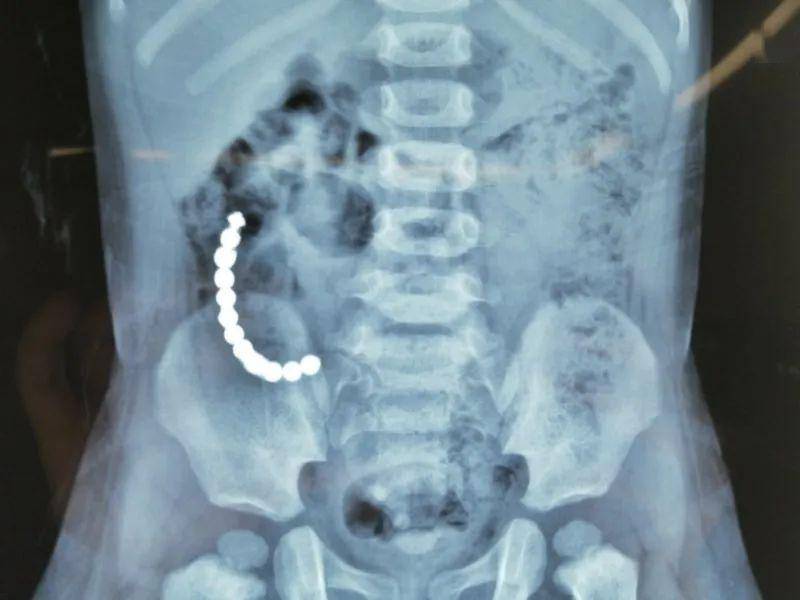

披着益智玩具外衣的磁力珠:

意想不到的肠穿孔隐患!

磁力珠看上去平平无奇,很无害的样子,被一些商家宣称为益智玩具,但小孩真的不太适合玩这个东西。

很多人会觉得,这不就是小珠子吗,吃下去应该能很快排出来吧?你错了,可别忘了它是有磁力的呀!

几颗小珠子一起吞下去,甚至可以连成一串,吸附力会对肠壁产生压力,可能引起肠胃穿孔或肠梗阻,需要做开腹手术才行,甚至有生命危险,太多的孩子因为这个东西进了PICU!